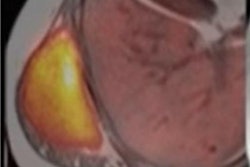

Image shows mean THK5317 and PK11195 nondisplaceable binding potential (BPND) for controls, rSRC and TBI patients, depicting tau and translocator protein (TSPO) expression, as well as corresponding standard deviation images. In symptomatic rSRC athletes, a voxel-wise t-test showed clusters of significantly increased THK5317 binding in the corpus callosum and subcortically including the medial temporal region and PK11195 binding in the medial temporal lobes. In TBI, elevated tau and TSPO binding was observed in the thalamus, temporal lobe white matter and midbrain. Significant group differences in total tau load were found between healthy controls and rSRC in subcortical grey matter (SRC 7.5 ± 0.9, controls 6.7 ± 0.5, p = 0.038), although not between TBI patients and controls. No significant differences in the number of voxels with THK5317 BPND > 0.5 or skewness in BPND distribution were found. Image courtesy of NeuroImage: Clinical.Ultimately, the results showed that PET tracers for tau and neuroinflammation can be used to identify long-term, postinjury increases in tau aggregation and microglial activation in young, symptomatic athletes with a history of three or more concussions, as well as in young adult patients with a single moderate-severe TBI. The data imply persistent pathology at prolonged postinjury time points and are supported by the increased CSF and serum NFL levels, the authors wrote.